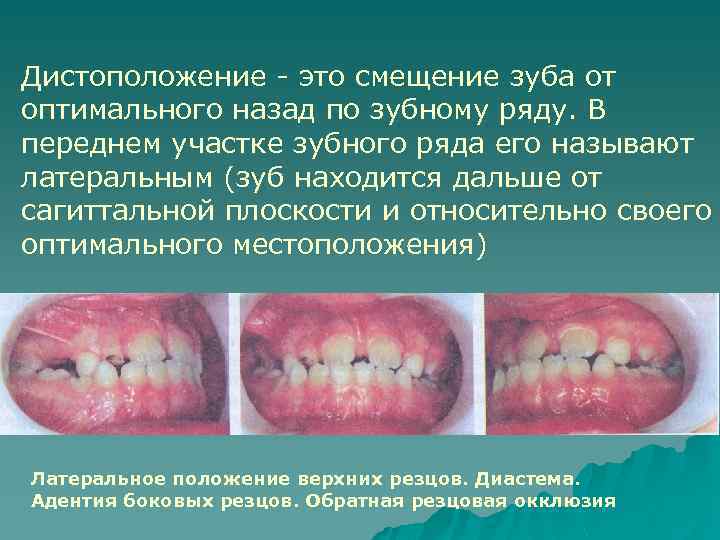

Дистоположение - это смещение зуба от оптимального назад по зубному ряду. В переднем участке зубного ряда его называют латеральным (зуб находится дальше от сагиттальной плоскости и относительно своего оптимального местоположения) Латеральное положение верхних резцов. Диастема. Адентия боковых резцов. Обратная резцовая окклюзия

Причины: частичная адентия, атипичное положение соседних зубов, нарушение прорезывания зубов, нарушение смены зубов, атипичное положение зачатков зубов, наличие сверхкомплектных зубов и т. д. Диагностируют при осмотре рта. Степень смещения устанавливают по смыканию с зубами-антагонистами, а также с использованием специальных диагностических методов.